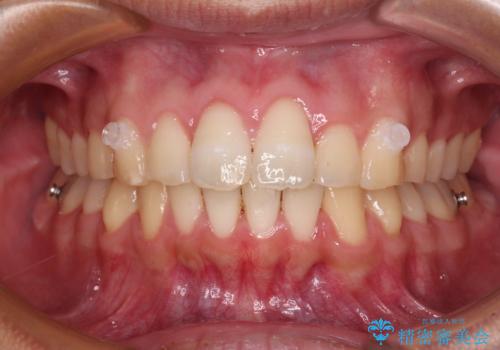

歯と歯の間を削ることでうまくスペースコントロールでき、また、毎日22時間以上しっかりとマウスピースを装着していただいたので、スムーズに治療が進みました。

治療途中で転勤となり、遠方からの通院となったため、来院間隔空いてしまいましたが、2年間で終えることができました。